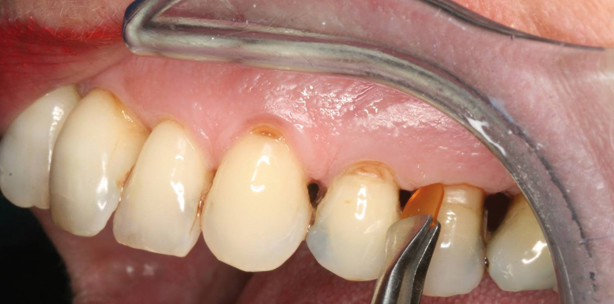

Ein Patient hat tiefe Zahnfleischtaschen, die Sie mit PerioChip zu ­behandeln empfehlen, da der Chip keine Antibiotika enthält, hochkonzentriertes Chlorhexidin sehr gut ­gegen paropathogene Keime wirkt, allgemein verträglich ist und kaum Nebenwirkungen oder Wechselwirkungen mit anderen Medikamenten zeigt. Unser Tipp: Mit Intraoralkameras z.B. können Sie den Befund zeigen und dem Patienten dabei ruhig und verständlich erklären, was passiert, wenn er keine Behandlung bekommt, und welchen Nutzen es für ihn hat, Ihren Vorschlag zu akzeptieren. Sollte er noch Bedenkzeit wünschen, so lassen Sie sich zu Ihrer eigenen Sicherheit von Ihrem Patienten unterschreiben, dass Sie ihn aufgeklärt und Behandlungs- und Therapiemöglichkeiten besprochen haben. Geben Sie ihm Informationsbroschüren z.B. vom Hersteller mit nach Hause.

Patienten,   die   die ­Zusammenhänge schnell begreifen und an einer ­sofortigen   Behandlung in­teressiert sind, ist besser geholfen, den PerioChip sofort nach der Reinigung zu applizieren. Alles Weitere erledigt das 36 Prozent hochkonzentrierte Chlorhexidin direkt am Entzündungsherd. Der Chip wird lokal mit einer Pinzette appliziert und löst sich innerhalb von sieben bis zehn Tagen vollständig auf. Er gibt dabei das Chlorhexidin im Slow-Release-Verfahren an die Tasche ab. Eine äußerst komfortable ­Lösung, zumal die Tasche bis zu elf Wochen keimfrei bleibt, während sich das Zahnfleisch regeneriert und der Zahn so stabilisiert wird. Diese Behandlung kann auch als Intensiv-kur angewandt werden, um tiefe ­Taschen innerhalb von acht Wochen ohne belastende Operation oder Antibiotika in den Beobachtungs­status zu heben (siehe http://onlinelibrary.wiley.com/doi/10.1111/j.1600-051X.2011.01779.x/pdf). Jede Zahnarztpraxis sollte sich zukünftig auf ein älteres Publikum einstellen. Schließlich wächst die Zielgruppe der über 50-Jährigen stetig an. Im gleichen Maße steigt auch der altersbedingte Behand­lungsbe­darf. Der Trend geht ten­den-ziell weg von der Vollprothese hin zu kombiniertem Zahnersatz. Der Dreh- und Angelpunkt ist jedoch, die Patienten schon in der Praxis medi­zinisch optimal zu versorgen und sie zu motivieren, ihre Recall-Termine regelmäßig wahrzunehmen. Idealerweise bietet man deswegen eine hochwertige und medizinisch optimale Systemprophylaxe z. B. als Gesamtkonzept an und knüpft diese an engmaschige Recall-Termine, sodass der Gang zum Zahnarzt einfach in den Alltag integriert wird. Das klare Ziel ist der langfristige Funktionserhalt jedes Zahnes in ­jedem Alter.